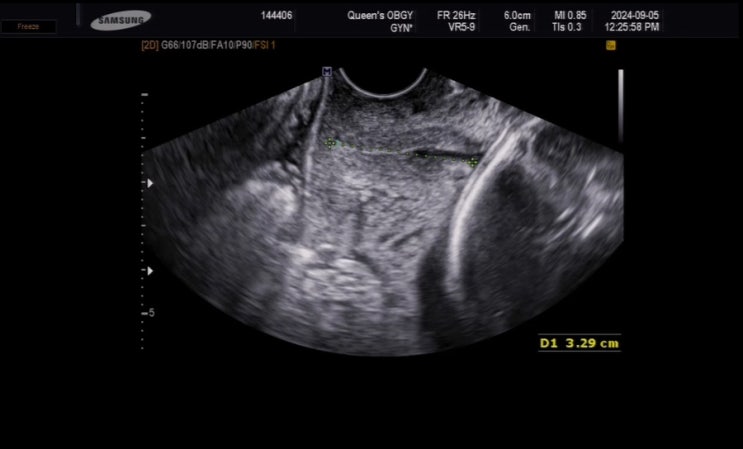

[임신기록] 30주 입체초음파

으아니? 벌써 30주라니 믿을 수 업쒀 !! 그치만 신나? 고대하던 입체초음파 예약날인데다가 오랜만에 친...